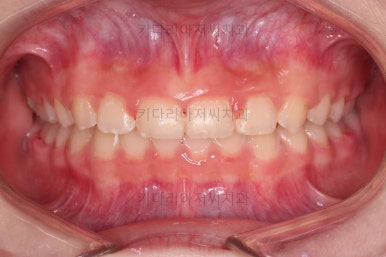

마무리를 해줍니다.

앞니 각도가 매우 좋아졌고요.(옥니 개선) 위 아래 앞니가 덮는 정도도 개선되었어요.(과개교합, 딥바이트)

엉성했던 어금니 맞물림도 매우 좋아졌어요.(앵글씨 2급 부정교합)

특히 옆라인에서 아래턱이 살아나면서 입매가 매우 예뻐졌어요.

부산교정병원 전후사진을 비교해 볼게요.

협조도가 요구되는 장치를 잘 못끼는 바람에 중간에 우여곡절이 있었고 힘든 과정도 있었지만 비교적 만족스러운 치료를 할 수 있었어요.